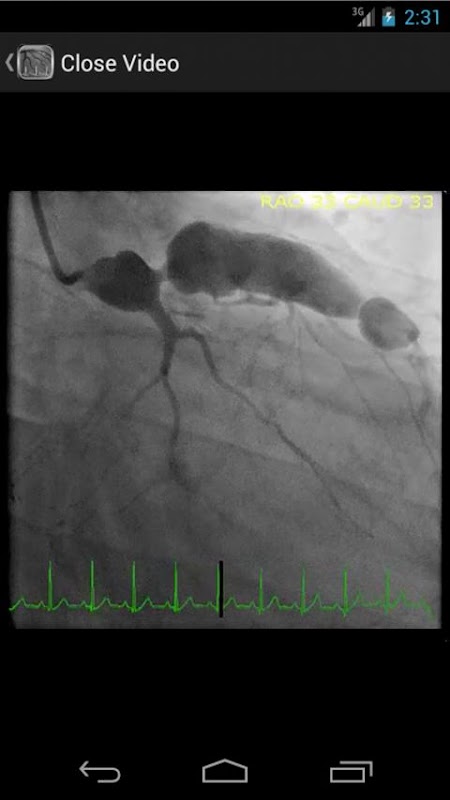

* Base de datos investigable que contiene más de 30 videos (angiografías coronarias, ventriculograms y aortogramas) de ambos resultados comunes y raras en el laboratorio de cateterismo cardíaco